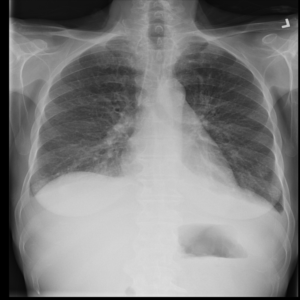

Figure 2: Examples of normal vs. abnormal images of considered datasets. Natural images: (first row) cars vs other classes of CIFAR10 dataset [1], (second row) digits “0” vs digits “1” – “9” of SVHN dataset [2]. Medical images: (third row) healthy tissue vs. tissue with metastases in H&E-stained lymph nodes images from Camelyon16 challenge [3], (fourth row) normal chest X-rays vs. chest X-rays with abnormal findings from NIH dataset [4].

Anomaly detection is a crucial task in the deployment of machine learning models, where knowing the “normal” data samples should help spot the “abnormal” ones [5, 6]. If an input deviates from the training data substantially (e.g., the input belongs to a class not represented in the training data), it is usually impossible to predict how the model will behave [7, 8]. This trait is especially important in high-consequence applications, such as medical decision support systems, where it is especially vital to know how to recognize the anomalous data. Identification of rare occurrences is another important application where anomaly detection is useful. For example, in pathology, where labeling diverse microscopy datasets is both time-consuming and expensive, the rare types of cells and tissues require specialized expertise from the annotator [9, 10]. Forthright anomaly classification and segmentation algorithms are typically prone to mistakes either because of the lack of sufficient annotation (thousands of labeled examples needed for supervised models) or because of the lack of representative data altogether (e.g., the case of some rare pathologies). Moreover, these algorithms are affected by the need to deal with very unbalanced and apriori noisy data, frequently leading to inaccurate results (e.g., the findings on chest x-rays can be so subtle that they can lead to disagreement in the interpretation [11, 12]). Because the normal cases greatly prevail over the abnormal ones, the anomaly detection could alleviate the annotation burden by automatically pointing to the rare samples.

In recent years, deep learning techniques achieved important advances in image anomaly detection [13, 14, 15, 16, 17, 18, 19, 20, 21]. However, these efforts were primarily focused on artificial problems with distinct anomalies in natural images (e.g., outliers in images of “cars” in the CIFAR10 dataset [1], see Figure 2). The medical anomalies, however, differ from those in the natural images [15, 19, 22]. Contrary to the natural images, the anomalies in the medical domain tend to strongly resemble the normal data. For example, detection of obscure neoplasms in chest X-rays [4] and of metastases in H&E-stained lymph node images [3] manifest a blatant challenge at hand, with the anomalous tissues being barely different from the normal ones (see Figure 2). Although deep learning has proved useful for a variety of biomedical tasks [23, 24, 25, 26], only recently, a few groups started dedicating their effort to the anomaly detection problem [15, 19, 27]. However, to the best of our knowledge, a thorough comparison of the state-of-the-art (SOTA) solutions in the medical domain is still missing despite the pressing demand and the prospective clinical value.

Anomaly Detection on Chest X-Rays

Chest X-ray is one of the most common examinations for diagnosing various lung diseases. We considered the task of the recognition of fourteen findings, such as Atelectasis or Cardiomegaly, on the chest X-rays in the NIH dataset (ChestX-ray14 dataset) [4] (Figure 2). Searching abnormalities on a chest x-ray is challenging even for an experienced radiologist since abnormality may occupy only a small region of lungs, or be almost invisible. The dataset consists of 112,120 frontal-view images of 30,805 unique patients: 86523 for training, 25595 for evaluation. We split the dataset into two sub-datasets having only posteroanterior (PA) or anteroposterior (AP) projections, because organs on them look differently. We tried different preprocessing during the hyperparameter search: rescaling to 256x256, 128x128, and 64x64 and histogram equalization, central crop (3/4 of the image size) to delete “noisy” borders. We considered images without any disease marker as “normal” and used them for training. Abnormal images for hyperparameter searching comprised of the training images of the most frequent disease (‘Infiltration’) out of fourteen possibilities. We also evaluated model on subset containing “clearer” normal/abnormal cases (provided by  [22]). This subset consists of 4261 normal images for training, 849 normal and 857 abnormal images for validation, and 677 normal and 677 abnormal images for testing.